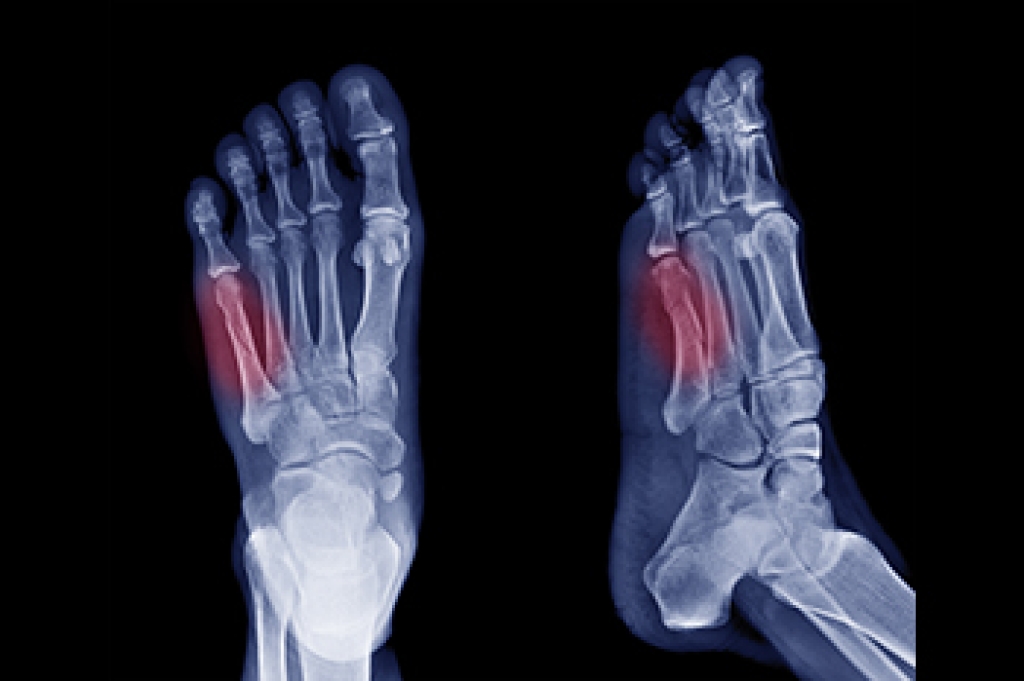

Symptoms of a Jones Fracture

A Jones fracture occurs in the fifth metatarsal bone of the foot and has distinct symptoms that necessitate prompt medical attention. Typically caused by a severe direct impact, this avulsion fracture involves the tearing away of a bone fragment by tendons or muscles. Acute pain is often the primary indicator of a Jones fracture, and individuals experiencing persistent pain at the base of the foot should seek immediate medical attention. Other symptoms associated with a Jones fracture include swelling, bruising, and impaired movement of the little toe. Contrary to common belief, movement may still be possible despite the fracture, but will be accompanied by significant pain. Impaired balance also can signal a potential Jones fracture, highlighting the importance of recognizing all symptoms. Swelling, typically localized around the fifth metatarsal bone and pinky toe is another indication of the likelihood of a Jones fracture. Typically, Jones fractures require approximately six to eight weeks to heal properly, and the foot may be immobilized in a cast during this period to promote optimal healing. If you suspect you may have sustained a Jones fracture, it is suggested that you make an emergency appointment with a podiatrist for a thorough evaluation, including X-rays, and appropriate treatment.

A broken foot is caused by one of the bones in the foot typically breaking when bended, crushed, or stretched beyond its natural capabilities. Usually the location of the fracture indicates how the break occurred, whether it was through an object, fall, or any other type of injury.

Common Symptoms of Broken Feet:

- Bruising

- Pain

- Redness

- Swelling

- Blue in color

- Numbness

- Cold

- Misshapen

- Cuts

- Deformities

Those that suspect they have a broken foot shoot seek urgent medical attention where a medical professional could diagnose the severity.

Treatment for broken bones varies depending on the cause, severity and location. Some will require the use of splints, casts or crutches while others could even involve surgery to repair the broken bones. Personal care includes the use of ice and keeping the foot stabilized and elevated.